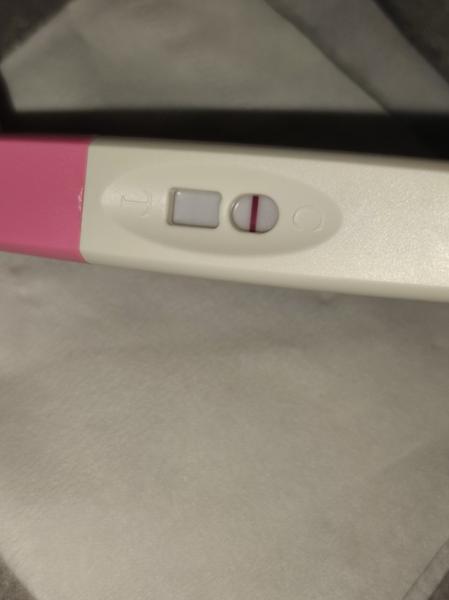

Duch na teste

ahojte babule, mam taku otazku...mate skusenost ze pocas 3 dni vam nesilnela druha ciarka na teste ale bola rovnaka???ako duch????

@zuzsat baby uvidíme na sono ideme týždeň tak uvidíme. Len určite aj trvalo tomu vajíčku sa vôbec spojiť čiže reálne to mohlo byt až v nedeľu večer niekedy, a ja som testovala minulý pondelok a tam nebolo nič ani duch na 9dpo, prvý duch bol až v piatok, čo bolo 13dpo a to vtedy ukázal aj digi test poobede. Tak ja stále nestrácam nadej do utorka 😊je vidieť že tie testy sú raz tak silnejšie po tých 2dnoch, a možno už aj ten digi by ukázal 2-3t, v piatok bolo 1-2 neviem nemám doma iný test okrem týchto z dm

@zuzanaa2010 si zlata ale nechce sa mi verit .. kym nie je poriadne vidiet stale budem na pochybach

@zuzsat ja takto..viem ze pepino robia duchov..ale druhy som namocila do vody a ten negativny🤣

Toto uz cisto zufalstvo🙊

@esmee3 je to individuálne, mne pri prvom silnela oveľa pomalšie ako pri druhom 😎 nestresuj sa zbytočne testami. Niekto už á ducha 9 DPO a niekto až 13 DPO 😉